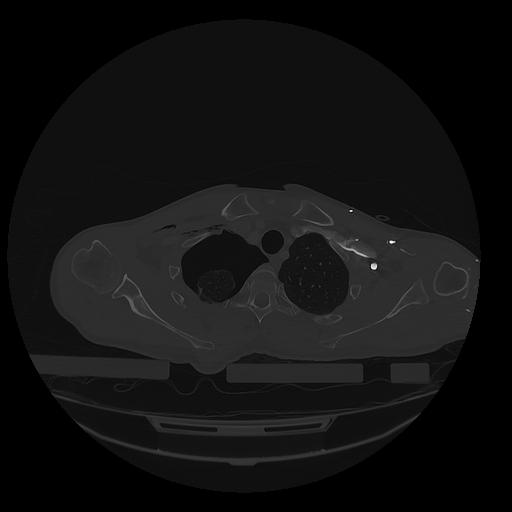

31 PULMON,CE,Vol,1.0,PULMON,,